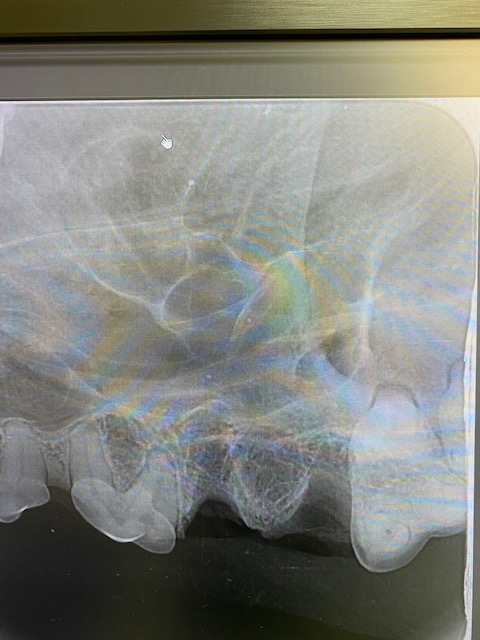

Slab fracture of 208x-ray at 45 degreesno sign of granuloma but as slab is below the gum line the tooth needs to be extractedInfraorbital and maxillary nerve blocks placedAll teeth descaled and polishedIncise to gingival junction with scalpel to distal edge of 209Place thumb on on infraorbital canal and make vertical incisionRaise a gingival flap using periosteal elevatorRound bur #6 to bur away buccal alveolar boneThe tooth sectioned at the furcationCrown removed and gutters cut using taper fissure burVet tome used to aid with extraction of distal root. Elevators and luxators also usedDistal root removed when looseDistal rootCrown height reduce on mesial roots until furcation visibleFurcation visibleBuccal root extracted with elevatorsTaper fissure bur used to remove the buccal bone of palatal rootPalatal root extracted using luxators, elevators and forcepsX ray to ensure all roots completely extractedRounded ends on sectioned roots indicate the root is fully removedCurette socketsFlush sockets with salineSmooth alveolar bone to ensure no rough edges with diamond football burMake periosteal releasing incision in the flap to ensure tension free closureSuture with 4/0 absorbable material simple interrupted patternClose up of extraction site after suturing